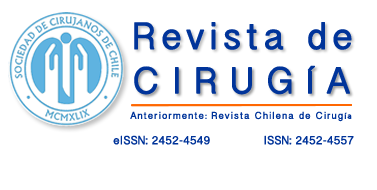

Imágenes y Cirugía

Caterina Contreras Bertolo, Javier Vela Ulloa, Felipe Bellolio Roth